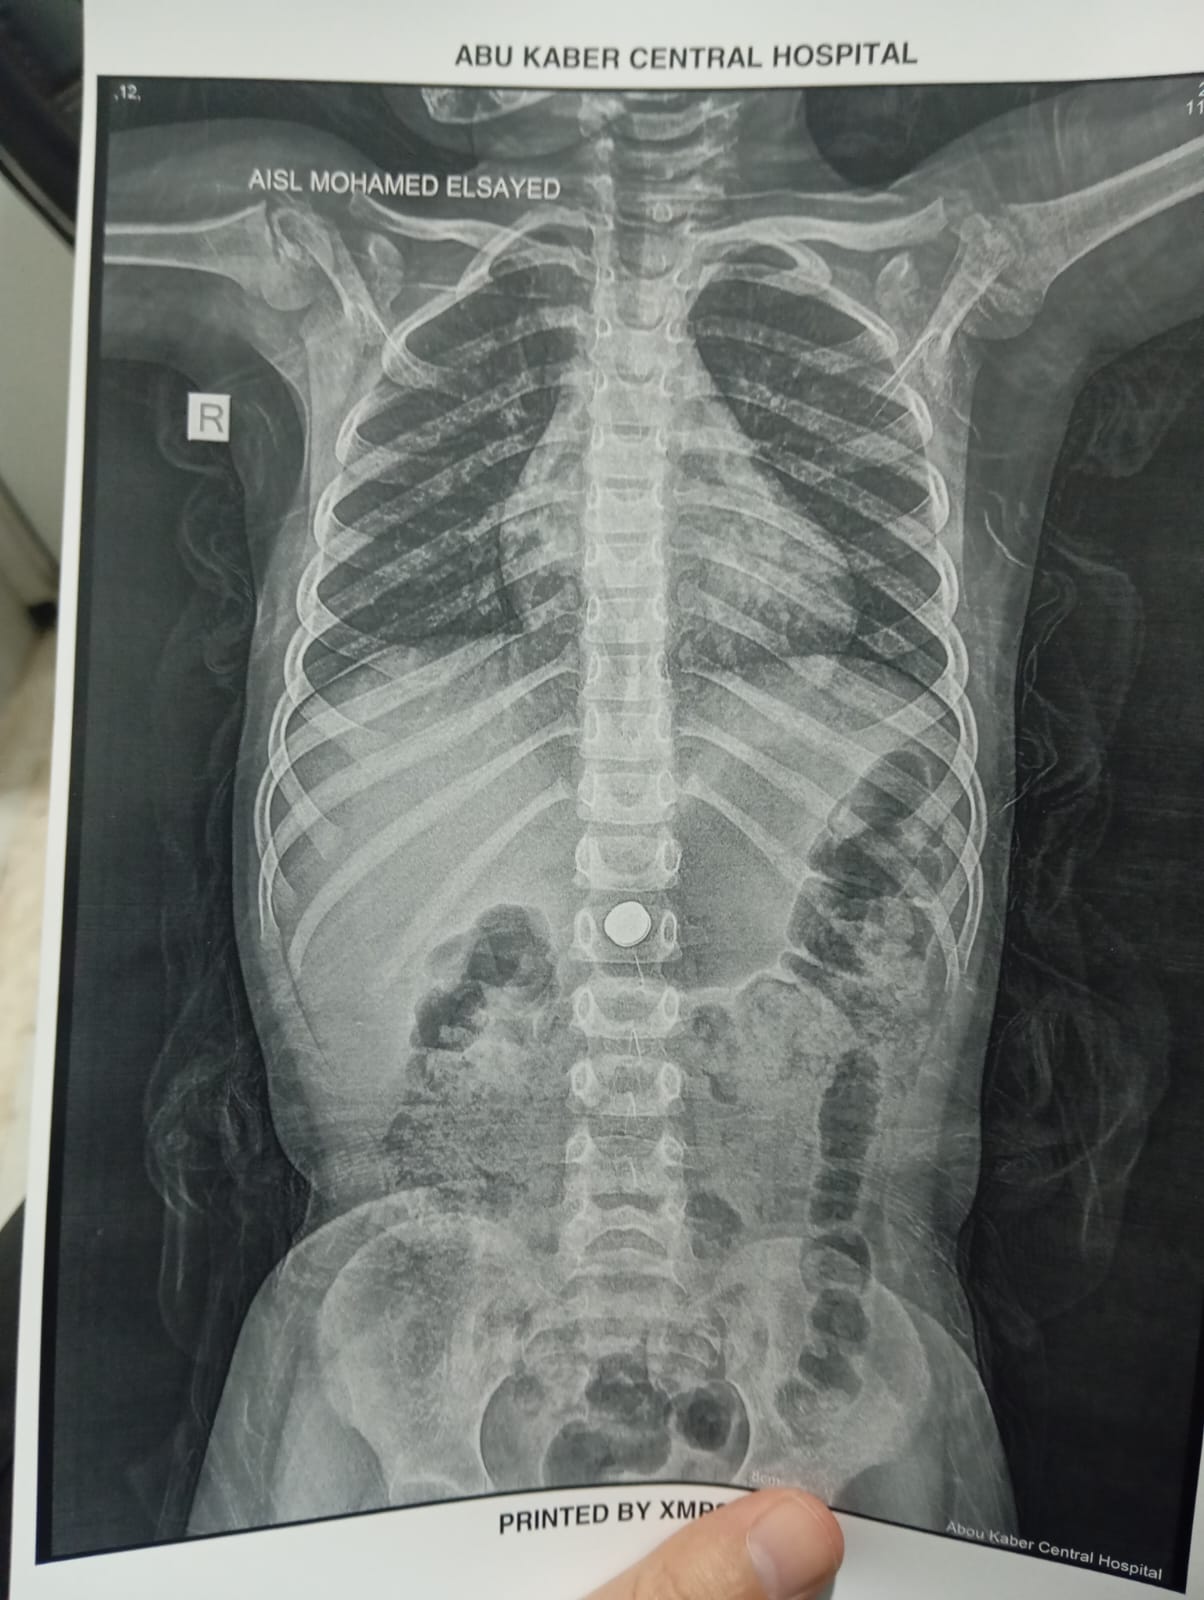

وأوضح الدكتور أحمد البيلي وكيل وزارة الصحة بالشرقية، أن الطفلة حضرت إلى قسم الاستقبال والطوارئ بالمستشفى بعد ابتلاع بطارية معدنية صغيرة، وهي من الحالات شديدة الخطورة التي قد تؤدي إلى حروق كيميائية عميقة بالمريء أو المعدة خلال وقت قصير، أو قد يصل الأمر إلى حدوث ثقوب أو نزيف حاد يهدد حياة الطفلة، نظراً لقدرة البطاريات على تفريغ شحنتها داخل الجسم خلال دقائق قليلة، مما استدعى سرعة التعامل الفوري مع الحالة وإجراء منظار ذات مهارة لها دون أي تأخير.

وأشار محمود عبدالفتاح مدير الإعلام والعلاقات العامة بالمديرية، إلى أنه فور استقبال الحالة، تم التنسيق الفوري من خلال مركز الخدمات الطارئة ١٣٧ بالمديرية، وتم تحويل الحالة إلى وحدة مناظير الجهاز الهضمي للأطفال، وإجراء كافة الفحوصات الطبية اللازمة لها، وإجراء منظار عاجل باستخدام التقنيات الحديثة، حيث نجح الفريق الطبي بفضل الله، في استخراج البطارية باستخدام شبكة المنظار، رغم صعوبة الحالة ووجود طعام داخل المعدة، وذلك مع الحفاظ على سلامة الأنسجة وعدم حدوث مضاعفات، وخرجت الطفلة بحالة عامة جيدة، وتحت الملاحظة الطبية للاطمئنان على استقرار حالتها.